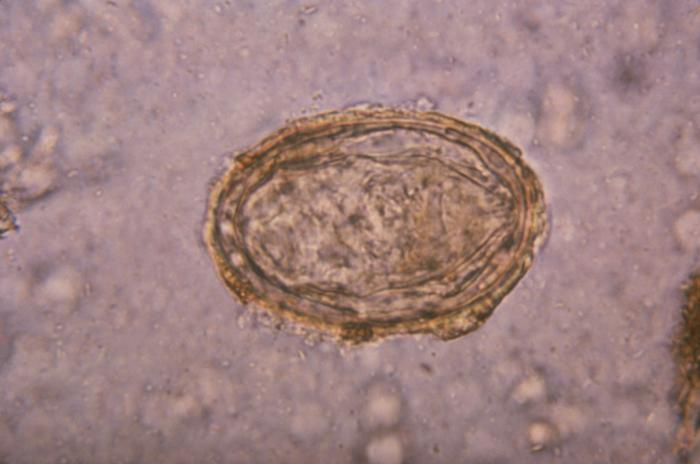

图注显微镜下的日本血吸虫

血吸虫并不是单独只寄生人类,大部分鸟类和哺乳动物都是它们的宿主,而主攻人类的也有几种,包括埃及血吸虫,曼氏血吸虫,日本血吸虫等等,在中国只有一种,那就是日本血吸虫。

血吸虫的一生会经历几个过程,成虫在人体内完成繁殖之后,它们的卵会通过尿液或者粪便排出体外(排出途径是尿液、还是粪便取决于血吸虫的种类)。

当这些排泄物流入水体时,它们就会开始孵化并释放出毛蚴, 毛蚴会寻找它的第一任宿主——蜗牛 ,对于*害迫**中国人的日本血吸虫而言它们寻找的是钉螺。